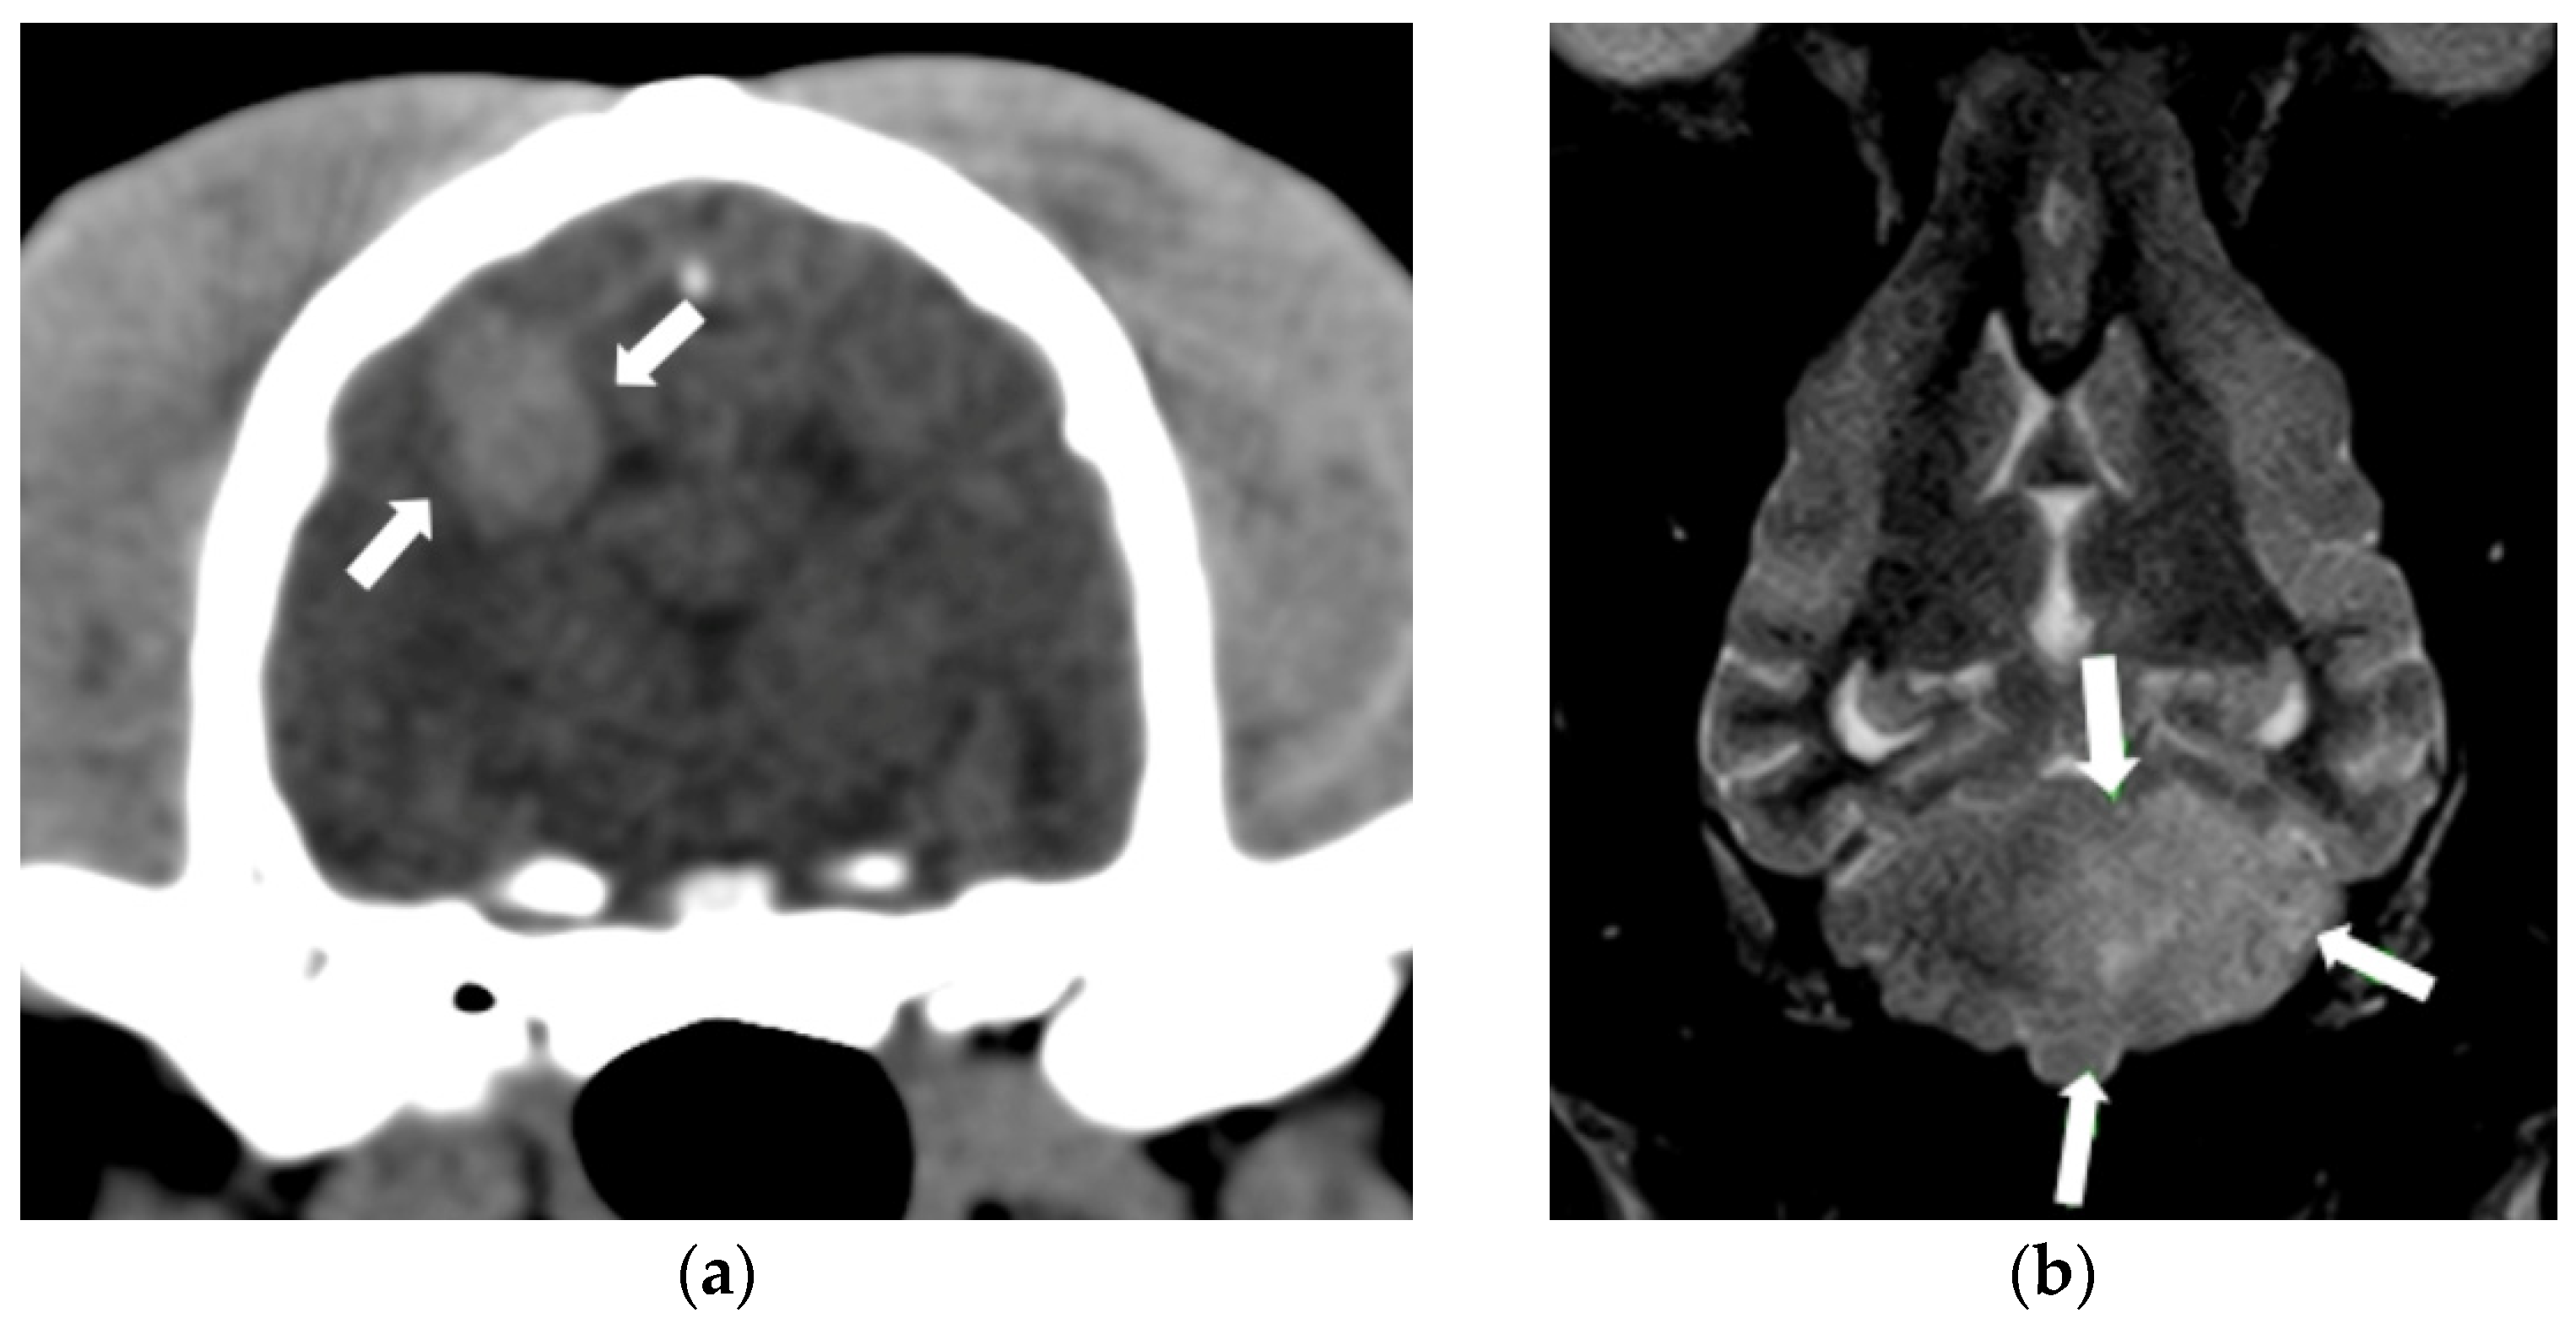

3.3. Spinal Cord Neoplasia